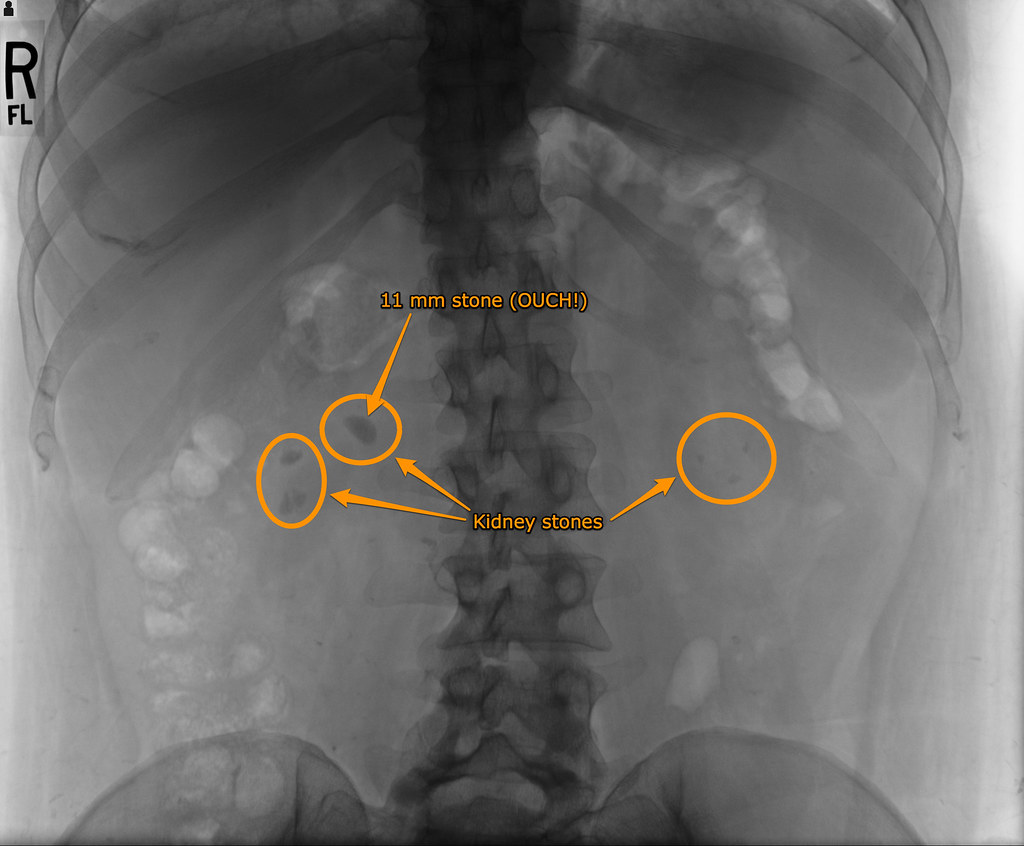

Symptoms include severe lower back pain, blood in urine, nausea, vomiting, fever, chills, and smelly or cloudy urine. Relevant and reliable information on the prevention, treatment and scientific explanation of kidney stones. Everything you need to know about what kidney stones are, what causes them to develop, and why some people are more likely to get them. Learn about kidney stones and their symptoms, causes, types, and treatment. Editors of consumer guide according to an old fairy tale, a single tiny pea placed be. Your kidneys are responsible for getting rid of all the toxins and waste byproducts floating around your bloodstream. Kidney stones can cause severe pain and other symptoms. Some are as small as the period at the end o. They form inside the kidney and can travel to other parts of the urinary tract. Over half a million people go to emergency rooms for kidney stone problems every year. Kidney infections (also called pyelonephritis) are a type of urinary tract infection (uti). Important to know is that not all kidney stones are alike. Kidney stones are solid masses of minerals and salt, usually made up of uric acid and calcium.